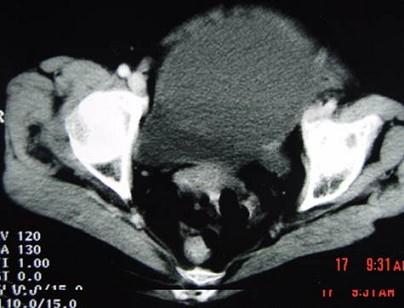

问题 55岁女性患者,腹胀腹痛消瘦一年余,行CT扫描如图所示,你认为最佳答案是 ( )

选项 A、卵巢浆液性囊腺瘤 B、卵巢囊腺癌 C、卵巢囊肿 D、卵巢粘液性囊腺瘤 E、卵巢表皮样囊肿

答案 B